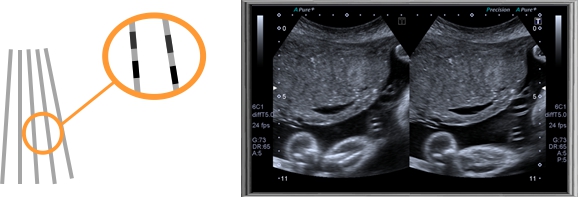

阿凡達采用多譜勒超聲成像技術(shù)和高精度數(shù)字波束形成技術(shù),融合組織諧波成像、斑點抑制、多波束并行等先進的圖像處理技術(shù)和高效的全數(shù)字圖文管理系統(tǒng)、輕松獲得更清晰的超聲圖像,專業(yè)化的測量軟件包可充分滿足臨床各種定量分析需求,靈活的配置和完全人體工學(xué)設(shè)計,提升了醫(yī)生臨床診斷的信心和臨床檢查的效率。

斑點智能抑制

自動識別和強化回聲信號中有效的組織特征信息,抑制并濾除噪聲,

提高信噪比,使圖像更清晰通透。

多波束并行處理

反射一條波束后,同時接收多個方向的回波信號,迅速提升圖像時間

分辨率,提高幀頻降低噪聲。